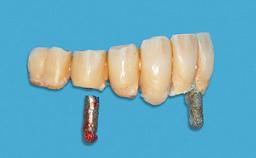

Improving an Existing Implant-supported Denture in an Alzheimer Patient with Bipolar Affective Disorder with Moderate Depression and Dementia

An 83-year-old man presented together with his caregiver at the dental department of the Medical University of Innsbruck, Austria with complaints of swelling in the right maxillary canine area and loss of retention of his 5-years-old mandibular denture. The patient had a significant medical history (20 years) of bipolar affective disorder with moderate depression (F 31.3) and dementia in Alzheimer’s disease (F 00.2). The patient had been in ambulant psychiatric therapy for his depressive illness for the past 20 years. He lived alone and had no children; his sister assisted with daily living. She reported that the patient exhibited compulsive hoarding behavior. In the previous two months, she had noted increasing disorientation and vertigo in the patient. She therefore accompanied him for a medical consultation at the Department of Psychiatry and Psychotherapy of the Medical University of Innsbruck. He was released home after a 6-week inpatient stay.

# of Implants 2

Type of Implants One-Piece

Attachment One-Piece

Prosthesis Type RDP